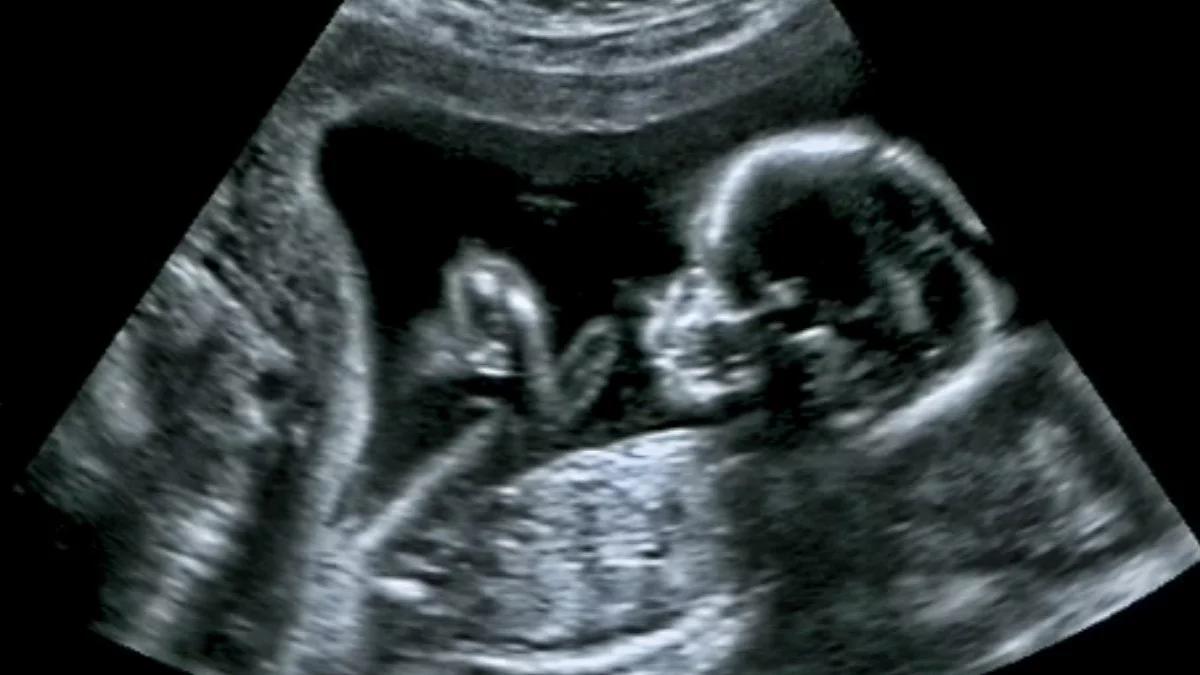

Zdjęcie ilustracyjne

Foto: shutterstock